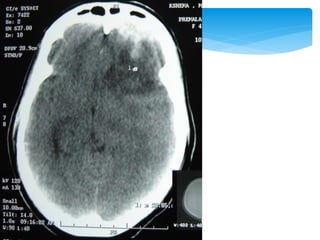

 Between the dura mater and inner table of the

skull; usually in the temporal or temporoparietal

region

 Tearing of the middle meningeal artery or, less

commonly, secondary to venous bleeding

 Directly related to the status of the patient before

surgery

 Close to 0 for patients not in a coma, 9% for

obtunded patients, and 20% for patients in deep

coma

Extradural Haematoma